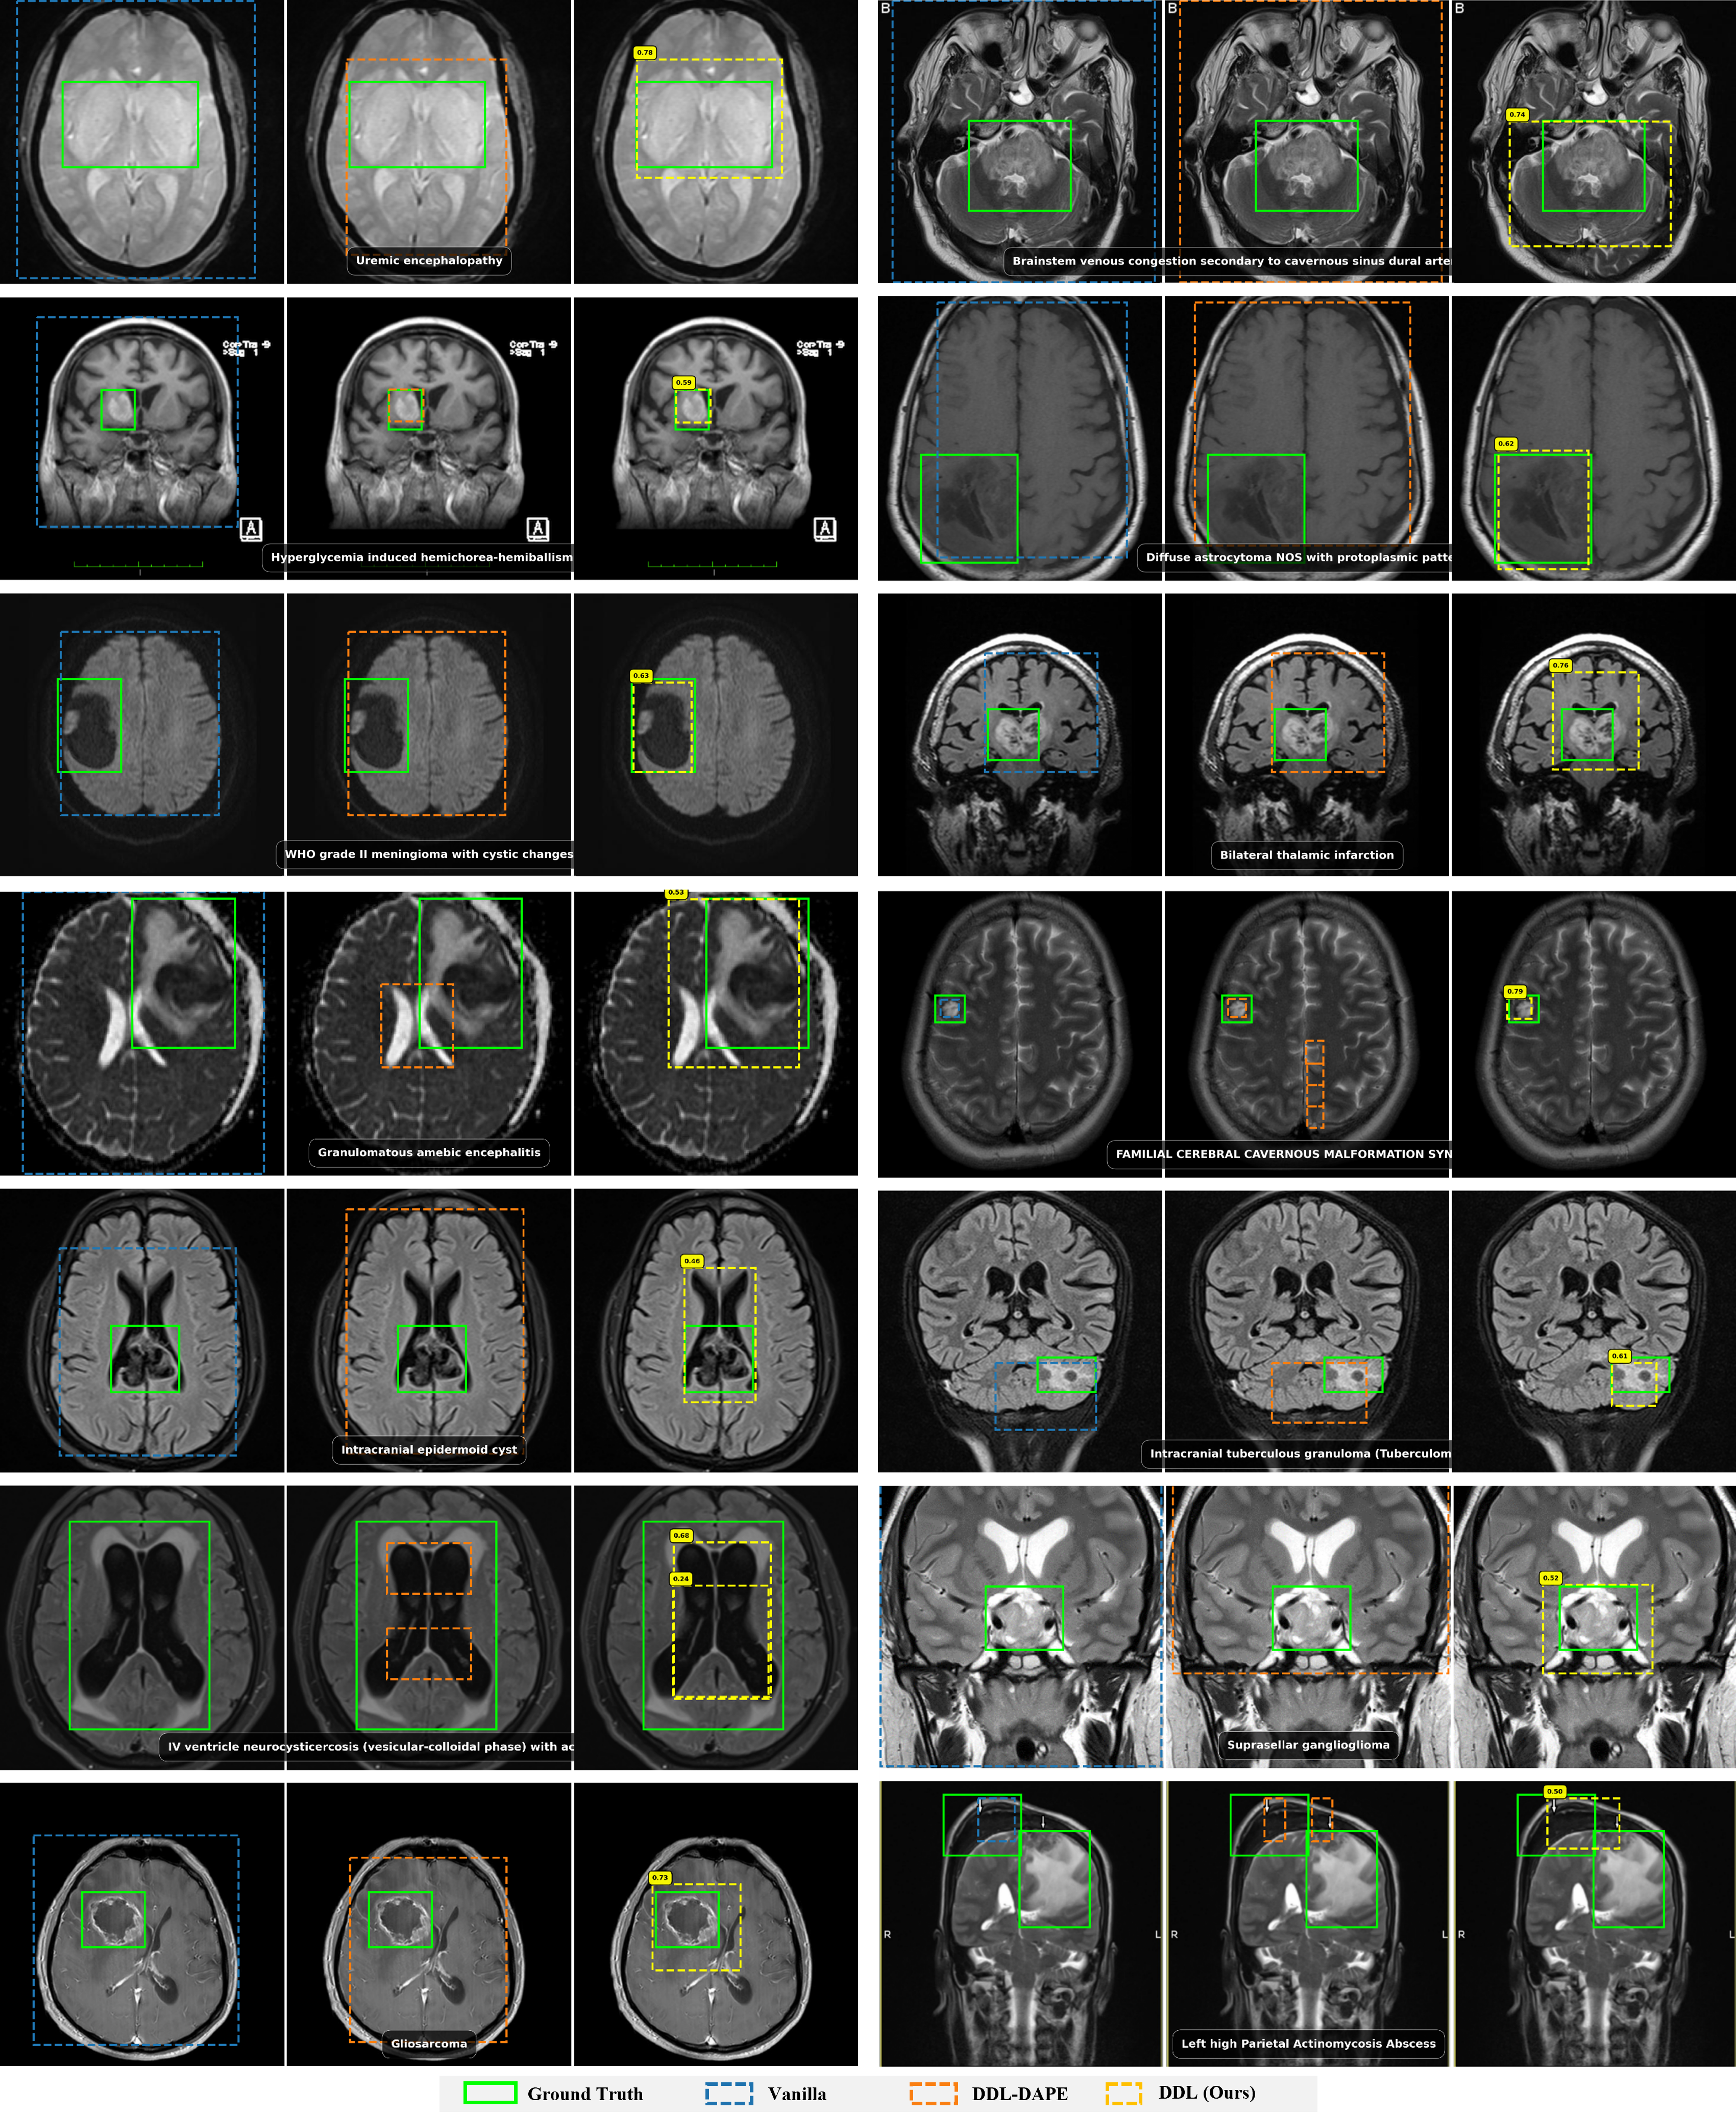

7B Results

Qwen2.5-VL-7B Grounding Performance